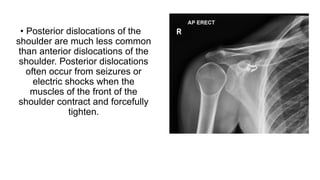

• Posterior dislocations of the

shoulder are much less common

than anterior dislocations of the

shoulder. Posterior dislocations

often occur from seizures or

electric shocks when the

muscles of the front of the

shoulder contract and forcefully

tighten.